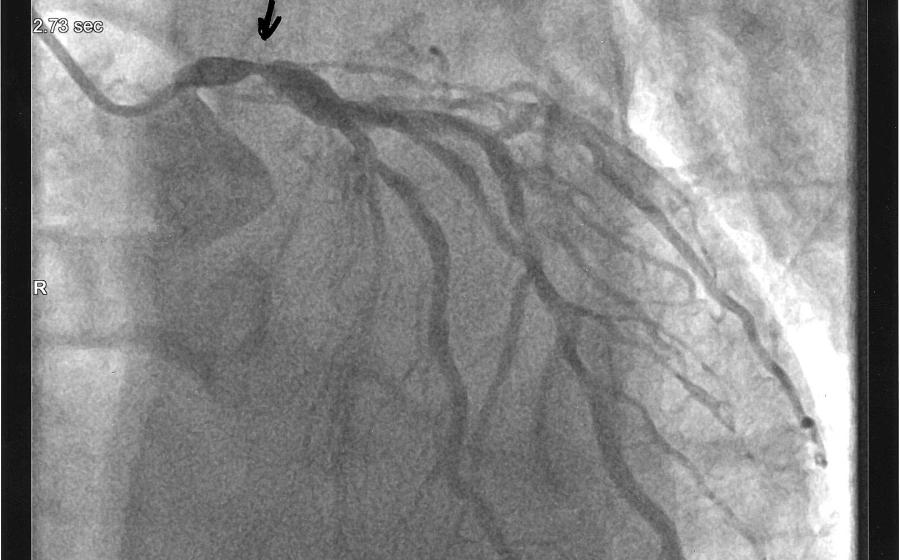

Scuba Diving & Heart Disease: Risks of Diving After Cardiac Arrest

In this installment, Eric Douglas explains what happens when you have a heart attack, and if it's safe to scuba dive after going into cardiac arrest.

Heart Disease and Diving: How To Make Long Term Lifestyle Changes

In this installment, Eric Douglas explains the relationship between heart disease risks and waistline, and explains what it's like to be in cardiac rehab.